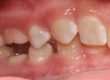

Клинични аспекти при прилагане на апарата Pendulum в смесено съзъбие

В тази статия си поставяме за цел да разискваме от клинична гледна точка позитивите и негативите при ползване на апарата Pendulum в смесено съзъбие. Ще разгледаме становищата за работа с апарата в случаите, когато са включени временните молари като опорна зона. Ще дадем какви са според нас клиничните предпоставки и индикации за използването на Pendulum в смесено съзъбие. Ще разгледаме терапевтичния протокол на няколко клинични случая, решени с прилагането на този апарат. Натрупаният от нас опит показва, че независимо кои зъби са в опорната зона се получава дистализиране на горни молари, но има разлики в не са значителни и не се отразяват негативно на основния ефект от действието на апарата Pendulum. Затова препоръчваме неговото ползване във всяка възраст и дентиция.